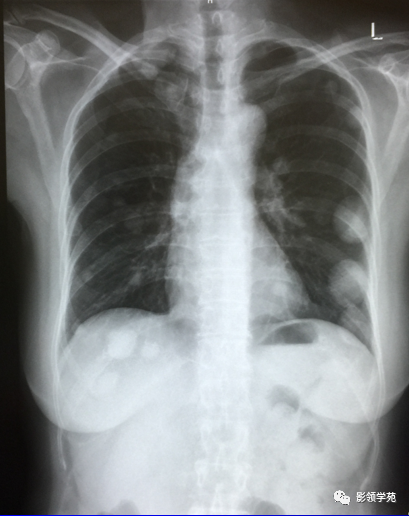

瘤外科患者,女,48,左乳癌根治术后2月术后化疗。病理:左乳伴髓样癌特征的乳腺浸润性导管癌。术后TAC方案化疗1个周期。

左乳切除术后,左肺下野两个大小不等高密度影。

1. 血行性转移 :多发或单发结节,大小不一,边缘较清楚。少数结节伴出血时出现晕轮征,即有略高密度影像环绕结节,使病变边缘模糊。病变有钙化常见于骨肉瘤或软骨肉瘤转移。转移瘤亦可表现为空洞。两肺多发的小结节影具有随机分布的特点,HRCT显示结节位于小叶中心、小叶间隔、支气管血管束及胸膜,结节大小不均匀。